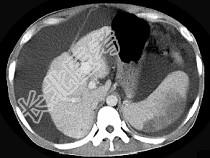

- 单项选择题患者男,29岁, 乙肝病史10余年,腹胀, 有移动性浊音,影像检查如图, 最全面的诊断是 ( )

A、肝硬化

B、肝硬化腹水

C、肝硬化腹水、脾梗、胆囊结石

D、大网膜膈下间位及脾梗

E、胆结石及脾梗